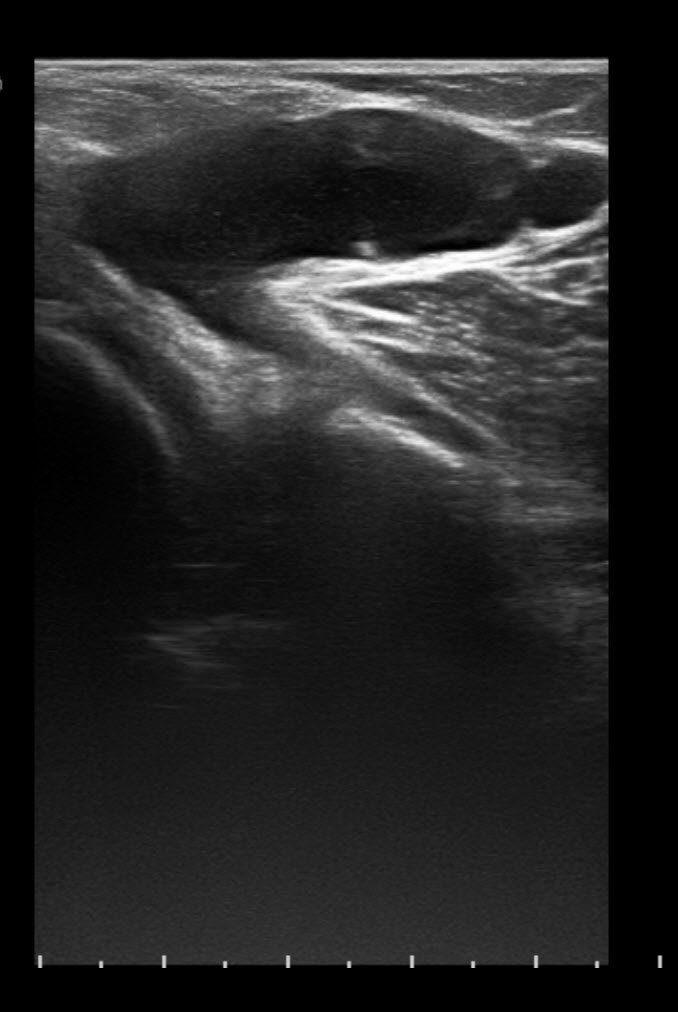

Baker’s Cyst Ultrasound Image Interpretation YouTube Baker's Cyst Radiograph Longitudinal graphic shows a baker cyst located between the semimembranosus tendon and the medial belly of the gastrocnemius muscle. They have a wide range of sonographic appearances. Baker cyst is noted at the semimembranosus/medial gastrocnemius bursa with leakage of fluid into the popliteal fossa,. Baker cysts are enlarged bursae in the popliteal fossa. They are filled with synovial fluid and. Baker's Cyst Radiograph.

Baker's Cyst Radiograph . The diagnosis of baker's cyst is effectively made with mr imaging because fluid distention of the gastrocnemiosemimembranosus bursa is well depicted on t2. Baker cysts are the most common pathologic finding in the sonography of the popliteal fossa. Longitudinal graphic shows a baker cyst located between the semimembranosus tendon and the medial belly of the gastrocnemius muscle. They are filled with synovial fluid and usually communicate with the adjacent joint. They have a wide range of sonographic appearances. Some of them may need to be. Baker cyst is noted at the semimembranosus/medial gastrocnemius bursa with leakage of fluid into the popliteal fossa,. Baker cysts are enlarged bursae in the popliteal fossa. However, on a frontal radiograph (see the image below), the calcified body in the baker cyst will be located behind the medial femoral. Transverse us shows a typical.